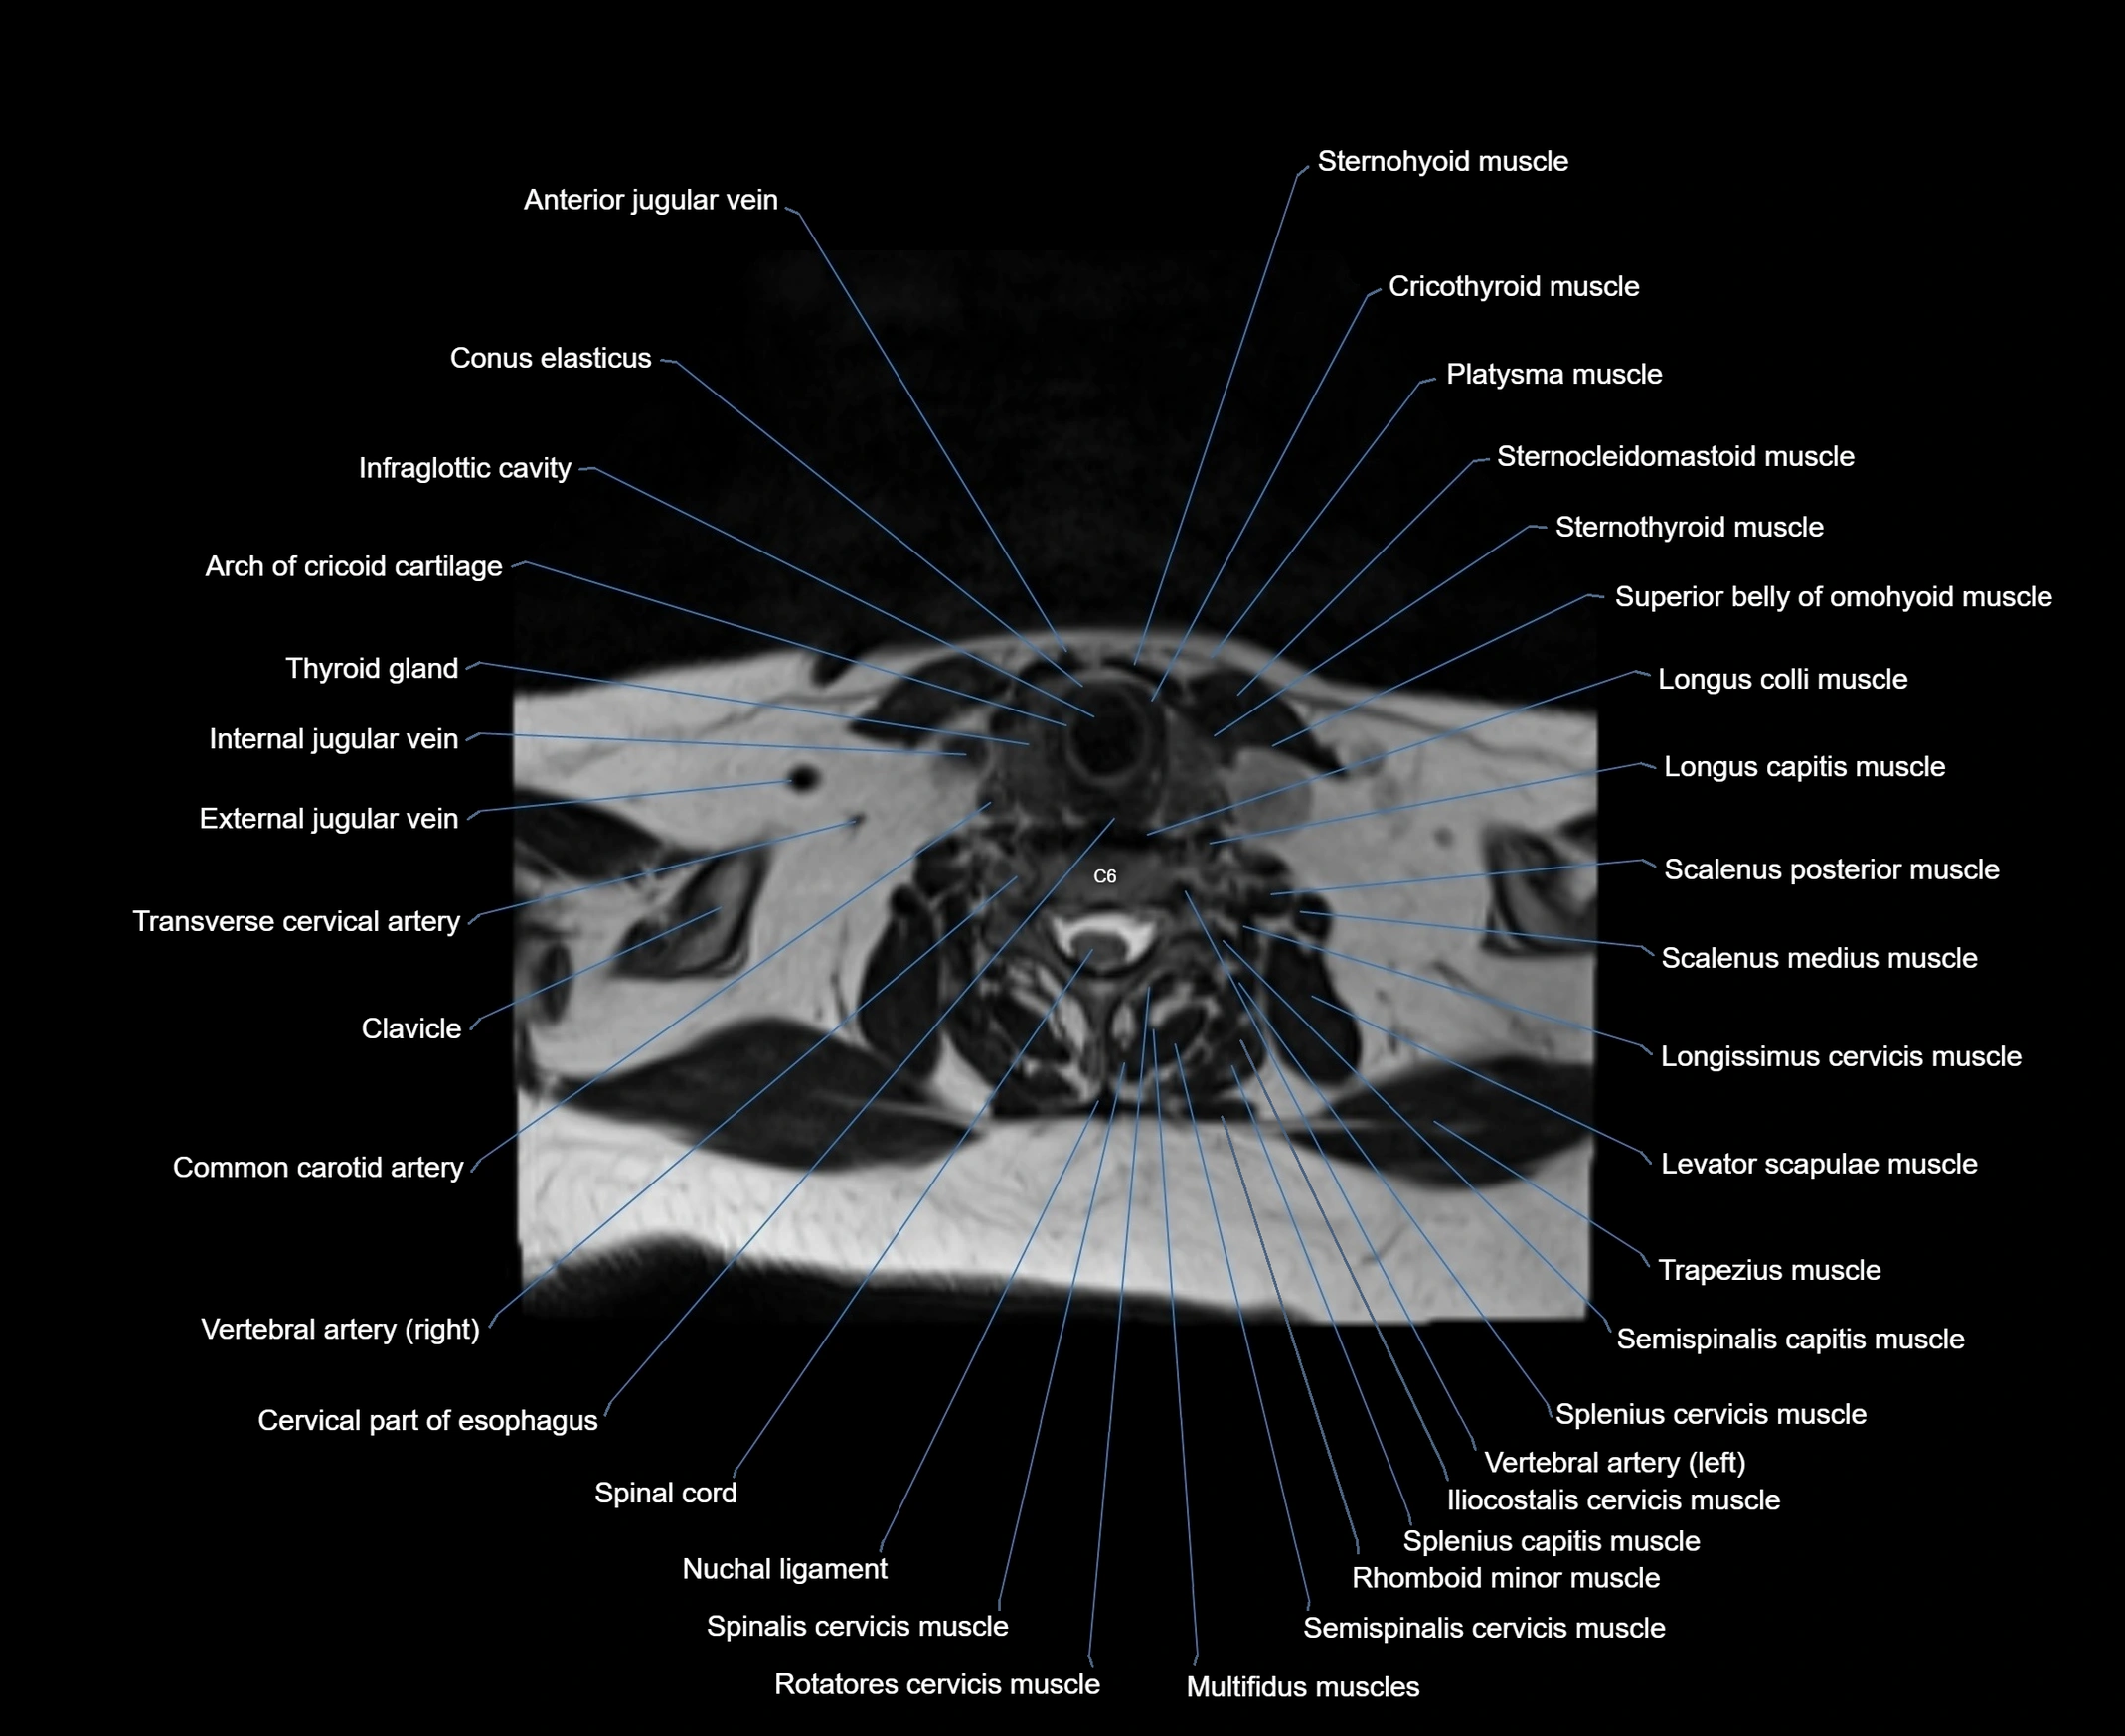

- Anterior jugular vein

- Arch of cricoid cartilage

- Common carotid artery

- Conus elasticus

- Cricothyroid muscle

- Iliocostalis cervicis muscle

- Infraglottic cavity

- Longissimus cervicis muscle

- Longus capitis muscle

- Longus colli muscle

- Multifidus muscles

- Platysma muscle

- Rotatores cervicis muscle

- Rotatores cervicis muscles

- Scalenus anterior muscle (Anterior scalene muscle)

- Scalenus medius muscle (middle scalene muscle)

- Scalenus posterior muscle (Posterior scalene muscle)

- Semispinalis capitis muscle

- Semispinalis cervicis muscle

- Spinal cord

- Spinalis cervicis muscle

- Splenius capitis muscle

- Splenius cervicis muscle

- Sternocleidomastoid muscle

- Sternohyoid muscle

- Sternothyroid muscle

- Superior belly of omohyoid muscle

- Thyroid gland

- Trachea

- Trapezius muscle